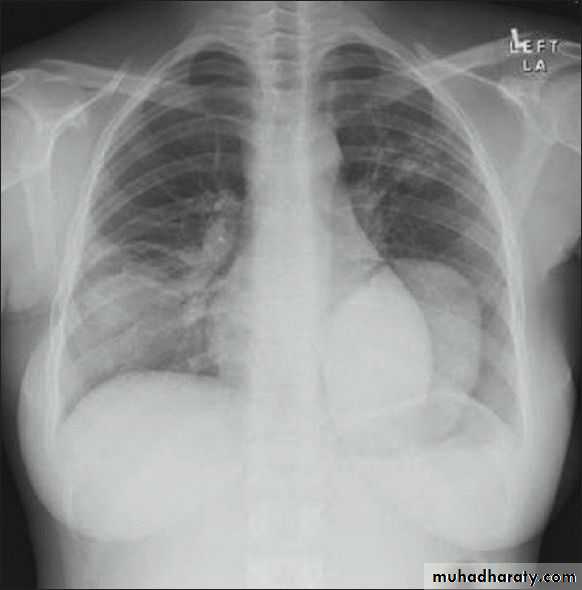

Diagnosis:

CXR

CT scan

thoracic surgery